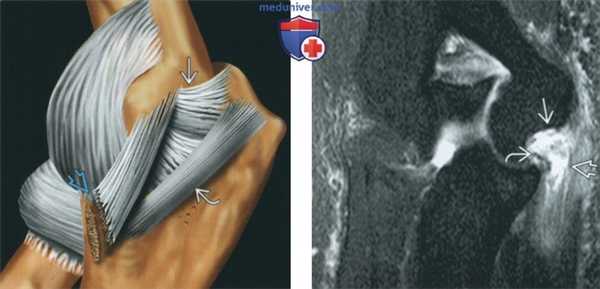

(Слева) На рисунке латеральной локтевой коллатеральной связки показана, что она начинается на латеральном надмыщелке плечевой кости, идет кзади от лучевой кости и прикрепляется дистально к гребню супинатора локтевой кости. Лучевая коллатеральная связка начинается непосредственно кпереди и прикрепляется к лучевой кости.

(Справа) На фронтальной МРТ PD ВИ виден ход нормальной латеральной локтевой коллатеральной связки. Латеральная локтевая коллатеральная связка отходит от латерального надмыщелка плечевой кости, обворачивается вокруг головки лучевой кости и прикрепляется к проксимальному концу локтевой кости.

(Слева) На фронтальной МРТ PD ВИ FS определяется полный отрыв общего начала латеральной локтевой коллатеральной связки и лучевой коллатеральной связки и сухожилия общего разгибателя от их места прикрепления на латеральном надмыщелке плечевой кости.

(Справа) На фронтальной МРТ Т2 ВИ FS можно видеть интактное начало латеральной локтевой коллатеральной связки с необычным разрывом на всю толщину дистальных волокон проксимальнее их прикрепления на локтевой кости. Связка обычно разрывается в проксимальном направлении.